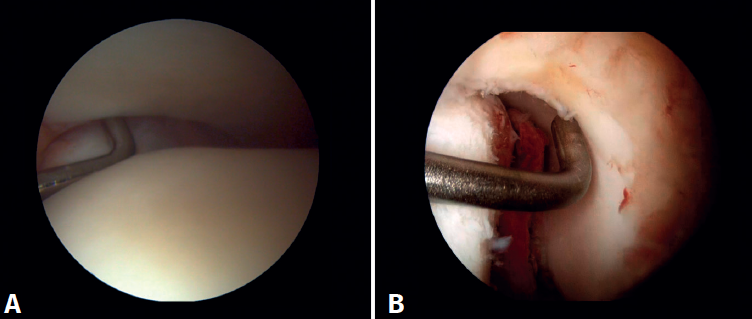

Arthroscopic evaluation of the syndesmosis

From the anteromedial portal we can directly visualize the distal fibers of the ATFL. Disinsertion of these fibers does not always result in instability of the syndesmosis, but it does require us to check it. In our experience, we prefer assessment of the coronal plane of the syndesmosis. We introduce the arthroscope into the tibiotalar joint directing the camera cranially. In this way we have a direct view of the distal tibiofibular joint. We then assess stability by attempting to insert the palpation probe into the joint. If it is possible to do so, we classify the syndesmosis injury as unstable (Figure 6A).

Arthroscopic evaluation of the deltoid ligament

There are multiple methods for assessing instability of the medial complex; using the anterior ankle portals it is possible to assess the stability of the deltoid ligament in its main plane of action, corresponding to the coronal plane. Chun et al.(20) described instability when it is possible to introduce an arthroscopic palpation probe into the medial tibiotalar space (Figure 6B). Vega et al.(21) reported that, in the majority of injuries, the most anterior portion of the deltoid ligament is detached from the medial malleolus, while its proximal insertions remain intact. In this situation, the arthroscopic palpation probe can be inserted between the medial wall of the internal malleolus and the deep fibers of the deltoid ligament.

Figure 6. Maneuvers to demonstrate ligament instability. A: lesion of the syndesmosis allowing insertion of the palpation probe into the distal tibiofibular zone; B: lesion of the deltoid ligament allowing insertion of the probe into the medial tibiotalar space.